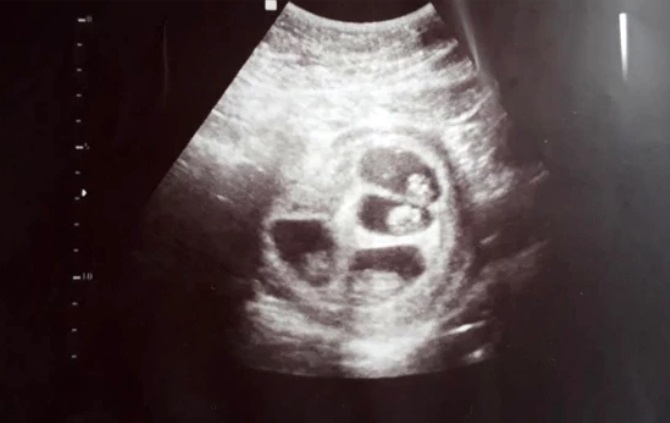

"Así que fuimos a hacer la ecografía. La ecógrafa me puso el gel en la panza y, apenas miró el monitor, se le transformó la cara. Miraba la pantalla, abría grande los ojos y repetía: 'No puede ser'. No dijo nada y salió a buscar a más médicos", cuenta. "Miré la pantalla y pensé que era cáncer, pensé que todo eso que se veía eran tumores y no había sabido cómo decírmelo".

Luciano se quedó en silencio cuando su novia lo miró asustada. "Yo también pensé que le habían encontrado una enfermedad", confiesa a Infobae. La ecógrafa volvió a entrar al consultorio acompañada de un obstetra y otra especialista en diagnóstico por imágenes. "Decían 'no puede ser, mirá', 'uhh' 'siii, es así', 'nunca vi algo así'. Estaba tan asustada que no me animaba a preguntar".

Cuando se animó a preguntar qué estaba pasando, la respuesta fue: "Bueno papis, están esperando cuatro bebés. Parece que dos son gemelos y los otros dos son mellizos". Jéssica empezó a llorar: "Pensé 'mi mamá me mata'. Estuvimos todo el viaje de vuelta pensando excusas, porque le habíamos dicho que íbamos al gastroenterólogo. Pero se ve que ella ya sospechaba y nos estaba esperando en la puerta".

La siguiente ecografía mostró que cada uno estaba gestándose en una bolsa diferente. Y pese a que le dijeron que era probable que pasara el embarazo internada y que alguno de los cuatrillizos no llegara a desarrollarse, los bebés -dos varones, una nena y un dudoso- están mejor de lo que esperaban. El más grande ya pesa 1,405 kg, el que sigue 1,210 kg., el otro 1,200 kg. y la nena 957 gramos.